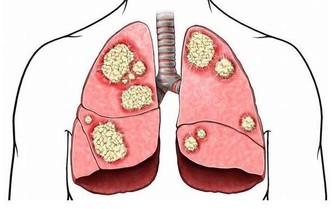

他包括泌尿系統、生殖系統、內分泌代謝系統、神經精神系統及消化、血液、呼吸等諸多系統的相關疾病。